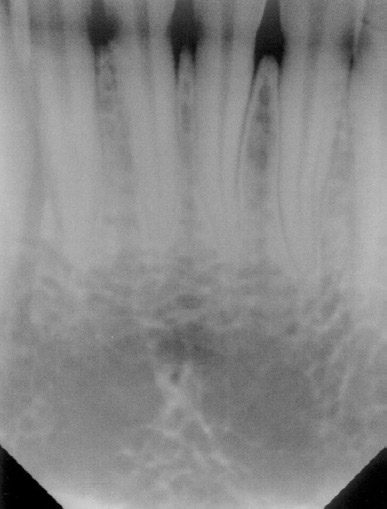

Figure 4. One of the most frequently reported intraoral digital imaging errors is cutting off of the teeth crowns. This error is more common with rigid intraoral sensors than flexible plates.

Figure 4

Common errors—As with any imaging technique, errors can be produced when the clinician fails to place the receptor properly or align the x-ray beam in the correct vertical and horizontal angulation or center the x-ray beam over the receptor. Therefore, it is possible to produce image foreshortening, elongation, overlapping, cone cuts, and inadequate coverage of the crowns or apices of the teeth (Figure 4). Ultimately, the technical quality of digital images as with film-based imaging is dependent on the skill of the clinician.

Several studies have identified some difficulties associated with the placement of rigid receptors. Versteeg et al27 found a significant increase in horizontal placement errors, especially in molar regions, and vertical angulation errors in the anterior segments that cut off the incisal edges of the teeth. Other studies have documented similar findings in horizontal placement and vertical angulation errors as well as cone cuts and difficulties with vertical bitewing placement resulting in missed structures and patient discomfort.28-30 Storage of phosphor plates present other image problems. Although the plates are flexible and thinner like film, they are susceptible to the production of image artifacts by abrading the emulsion during handling and erasure.21